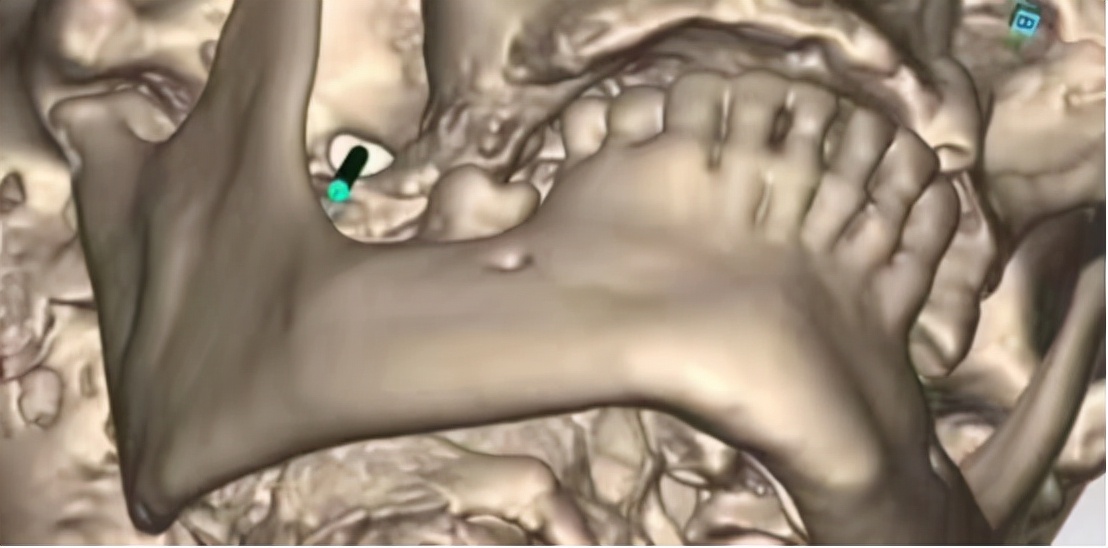

8月30日,由华安脑科医院院长傅先明教授、副院长杨先清教授、谢英贺副主任等神经外科组成的专家团队经过讨论,在征得家属同意后,决定为刘奶奶进行DSA引导经皮穿刺三叉神经半月节球囊压迫术。

该手术是经面部皮肤穿刺到达三叉神经半月节的部位,通过球囊导管适度压迫,达到控制疼痛的效果。整个创口仅一针眼大小,在我院引进的美国GE双板DSA的影像设备精准定位下完成,该设备一次注射造影剂同时显影正、侧位血管影像,可清晰显示血管造影。